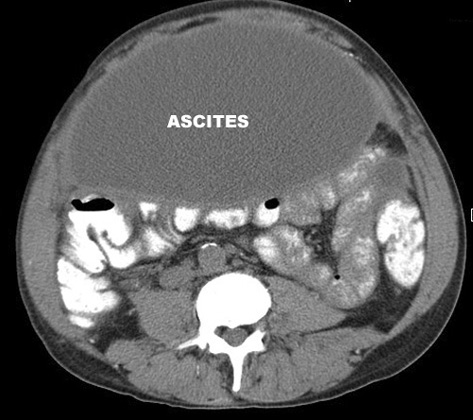

Вільна рідина в черевній порожнині

Вільна рідина в черевній порожнині може свідчити про різні патологічні стани, такі як асцит, кровотеча або запальні процеси. КТ допомагає визначити обсяг та локалізацію рідини, що є важливим для діагностики та лікування.

| Вільна рідина | темна зона, без форми, повторює простір |